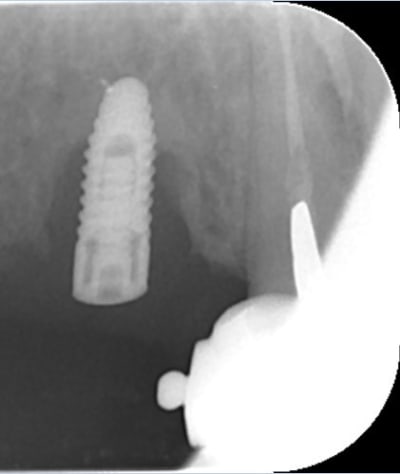

Mon petit cas galère du moment...

Péri-implantite 14 et 26.

25 explosée.

Infection apicale 13, 12, 33 (chaque 2 mois sous antibio depuis pas mal de temps...)

Et gros bouchon de fugy de 2 à 3 mm au fond du logement de l'inlay core, que j'ai dû traverser à la fraise diamantée pour pouvoir retraiter la 13 et la 12... :-)

Là, le dentiste (retraité depuis peu) a tout couronné, mis deux implants en plus pour rien, puis un stellite avec attachement (avec les implants en dessous qui ne servaient à rien...).

28/10/2014 à 23h43